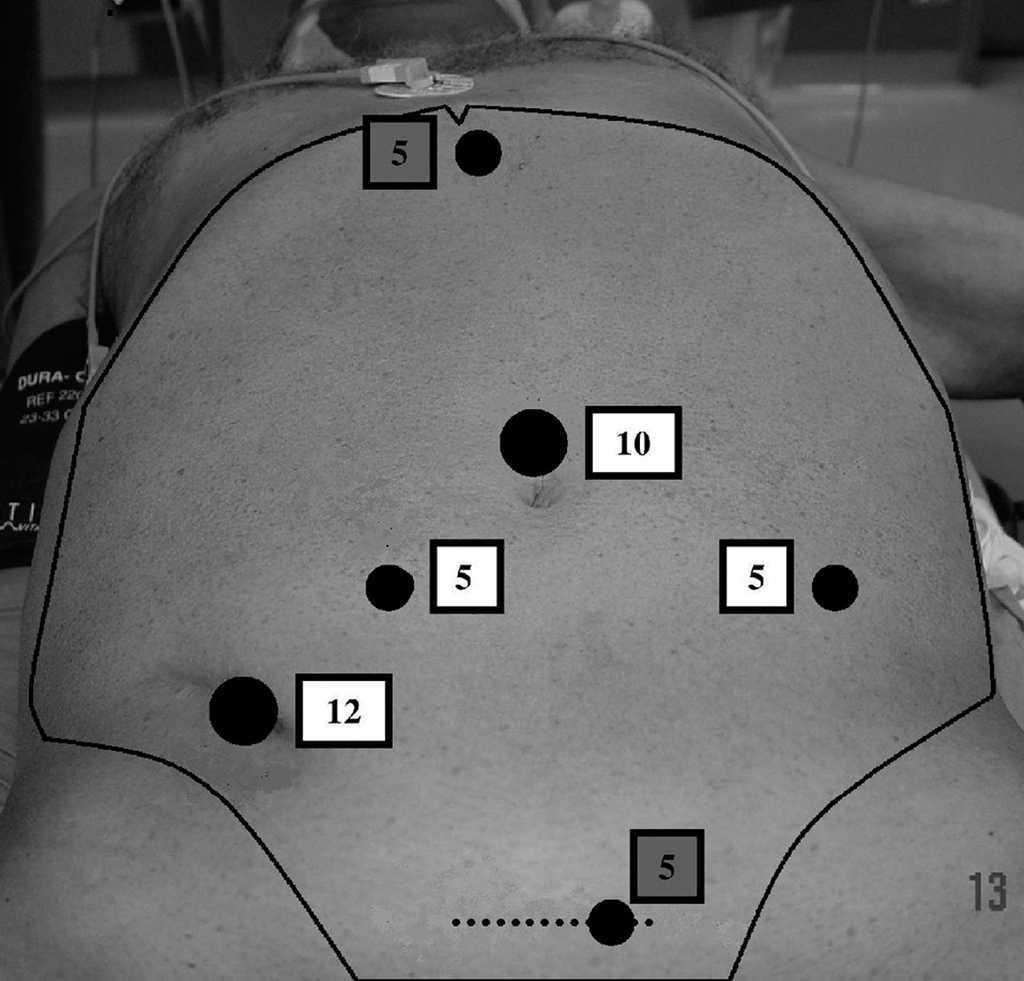

Los pacientes recibieron solución evacuante el día antes de la intervención y profilaxis antibiótica durante la inducción anestésica. Fueron intervenidos con anestesia general en posición de Lloyd Davis, con el brazo derecho extendido a lo largo del cuerpo. Se realizó neumoperitoneo a 14 mmHg de presión con aguja de Veress. Colocamos inicialmente 4 trocares, cuando realizamos exéresis total del mesorrecto disponemos de dos puertos adicionales (fig. 1).

Fig. 1. Disposición de los puertos de entrada. Obsérvese los puertos opcionales en región subxifoidea y sobre la herida de asistencia (resaltados en gris).